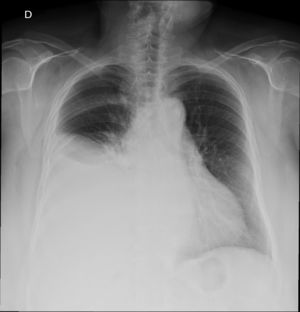

We present the case of a 70-year-old woman with a history of hypertension, type 2 diabetes mellitus, hyperlipidemia, and chronic kidney disease secondary to nephroangiosclerosis and/or diabetic nephropathy. The chronic kidney disease required peritoneal dialysis catheter placement. The catheter placement technique was done under local anesthesia and sedation, with no incidents. Three months after starting a peritoneal dialysis program, the patient came to the emergency room with dyspnea as the main symptom. A simple chest radiograph demonstrated a large right pleural effusion (Fig. 1). Thoracentesis and analysis of the sample obtained a glucose concentration higher than the plasma concentration. With a suspected diagnosis of pleuroperitoneal communication, scintigraphy with Tc-99 was requested, which confirmed the diagnosis (Fig. 2), and the patient was given a rest from dialysis and changed to hemodialysis. Given the lack of response to this approach, the catheter was definitively removed and the patient referred to a hemodialysis program.

Pleuroperitoneal communication is a rare entity in patients undergoing peritoneal dialysis. Its incidence varies according to the series (1.6%–10%), which may be due to the variable capacity to diagnose low-volume hydrothorax.3,4 Some authors report a higher incidence in women, as in the case presented, and in certain etiologies, such as polycystic kidney disease, which was not present in our patient.5 Regarding its location, the majority of cases are presented on the right side, as in the case presented, and bilateral presentations are exceptional.6 Some authors explain this finding as the existence of an embryonic remnant that allows the passage of fluids from the abdominal cavity to the right pleural space.7

This diagnosis should be suspected in patients on peritoneal dialysis who present dyspnea more or less abruptly and in whom right pleural effusion is observed on simple chest radiography.8 Analysis of the pleural fluid may show higher glucose levels than plasma glucose levels, which is a very indicative sign.9 The study is confirmed by a scintigraphy showing the passage of the radioactive isotope from the abdominal cavity to the pleural cavity.10 Treatment is fundamentally based on “peritoneal rest” and changing to hemodialysis temporarily or definitively, which may be accompanied by pleurodesis. Surgical treatment involving closure of the communication is the option least used, partially due to the limited relevance of this entity outside the scope of peritoneal dialysis.8 Similar to the case presented, most authors prefer conservative treatment, which achieves success in more than 50% of cases.3